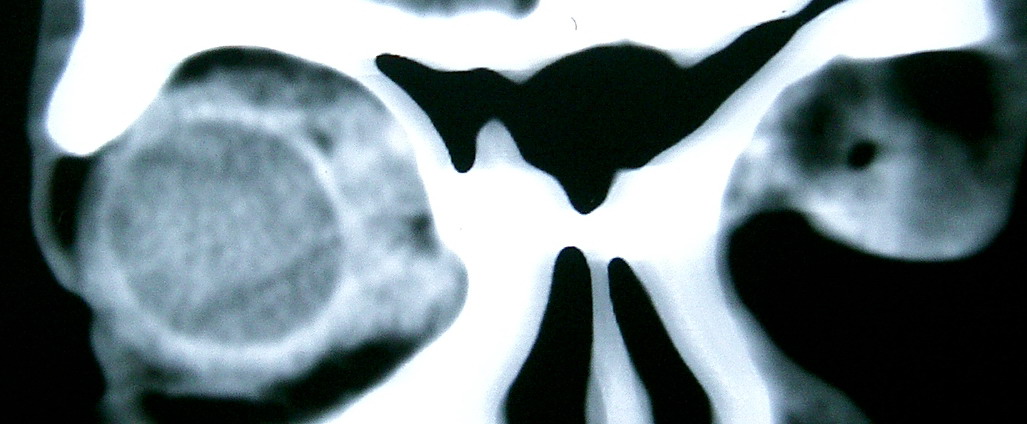

眼眶冠扫,平扫CT: 左眼球内上方可见不规则软组织块影,大小约2.5*1.0CM,与邻近组织分界不清,相邻之内直肌、上直肌增粗,眼环正常,眶壁骨质无破坏,左上颌窦底部可见粘膜增厚,其余副鼻窦未见异常。 IMP:1,左眼眶肿物;2,左上颌窦炎